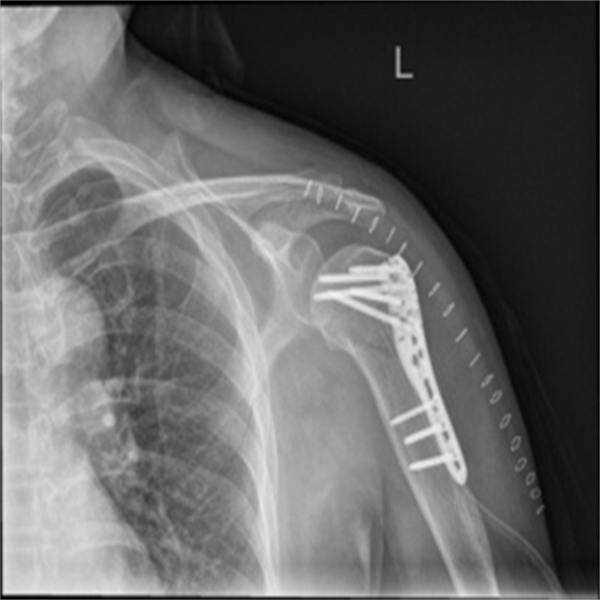

家住燕山东风的刘姐,生活幸福美满,一家人其乐融融。可是,一次意外将平静的生活打破了。一天傍晚,她在自家小区门口散步时,被一辆小轿车给撞倒了,当时右肩部剧烈疼痛,不能活动,很快就肿起来了。到北京燕化医院就诊后,拍片检查提示:右肱骨近端粉碎性骨折。刘姐不得不住院进行治疗。在经过几天的消炎治疗,刘姐肩部肿胀症状有所减轻,她顺利接受了手术治疗。

手术虽解决了刘姐肩部的骨折疼痛,但是术后肩部疼痛肿胀、关节活动受限却使刘姐犯了愁。如何快速的消肿,尽快的恢复日常生活能力,是摆在她面前的一个大难题。幸好,燕化医院的康复科与骨科建立了协作,刘姐这一顾虑,医生早已设计好了解决方案。术后即开始参与康复治疗,并为她制定了个性化的术后康复方案。在康复科医生和治疗师的共同努力下,刘姐的肩部肿胀很快消退,肩关节的日常功能活动得到了明显的改善。最终,在刘姐的坚持下,肩关节在短短的时间内,就拥有了很好的功能,不仅能够梳头洗脸,还能给自己挠痒痒。